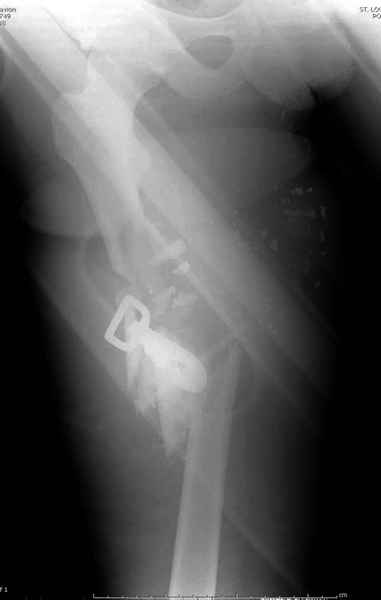

2 перелом бедра

На Вашем месте мы бы сделали ретроградний интрамедуллярный штифт. Нагрузка с первых дней не самоцель, хотя 12 мм штифт с двумя интерлокинг винтами выдерживает вес 75 кг., но разработку сустава можно начать как можно быстрее.

Достаточно пары месяцев для определения нужды в дополнительной костной пластики.